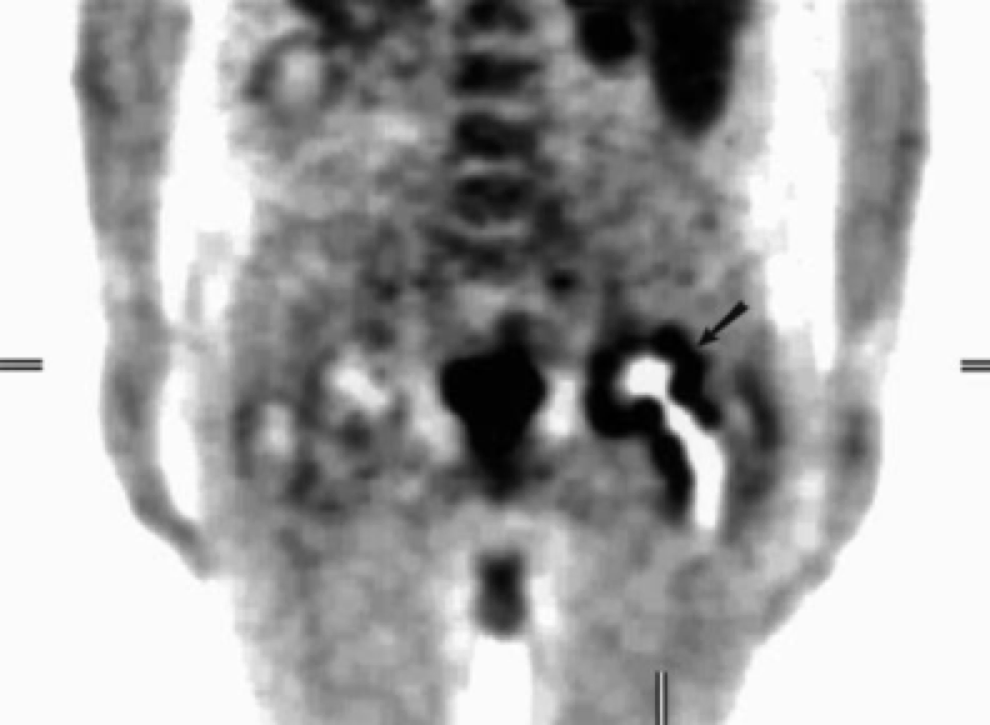

4.骨溶解:

发生率 5%~9%,与透亮线不同,地图样透亮区是由假体相关的骨水泥、金属或聚乙烯颗粒诱导的组织炎症反应所致(颗粒病)。

右侧髋臼及耻骨支骨质溶解吸收,关节周围团块状软组织肿块,围绕股骨头及股骨颈